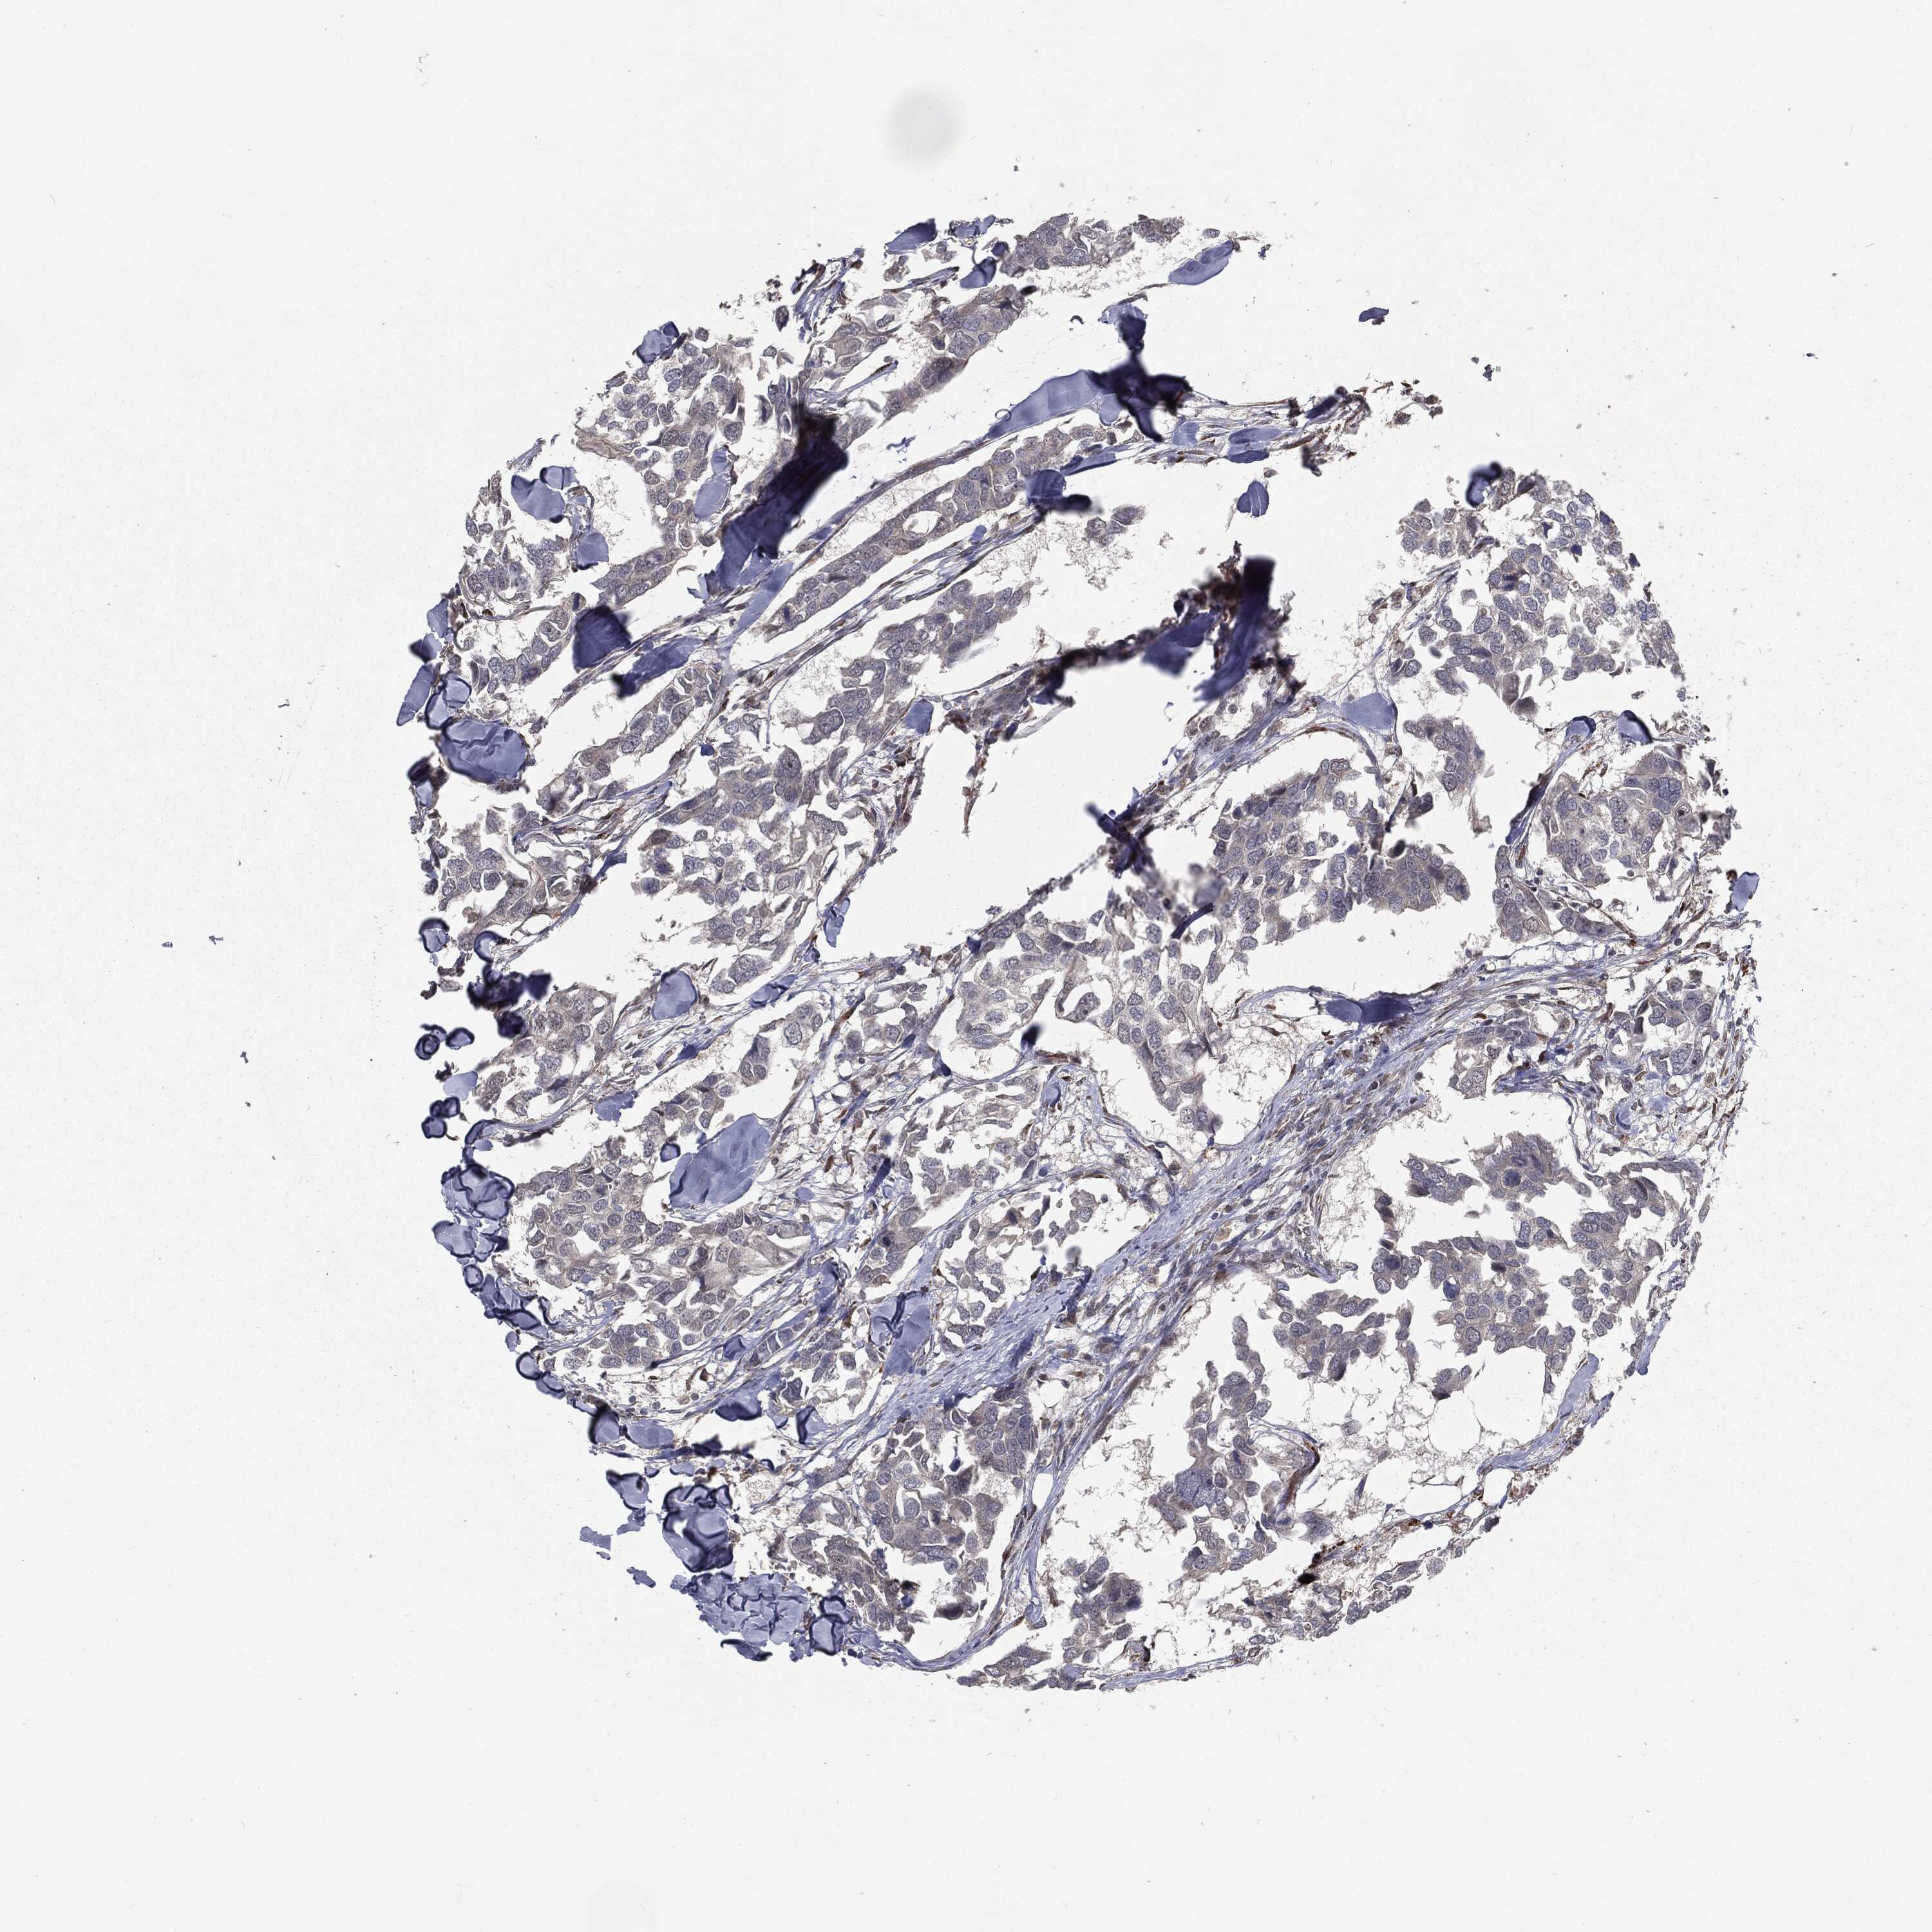

BRCA TCGA BRCA VALIDATION PROTEIN EXPRESSION

Breast cancer

Human cancer